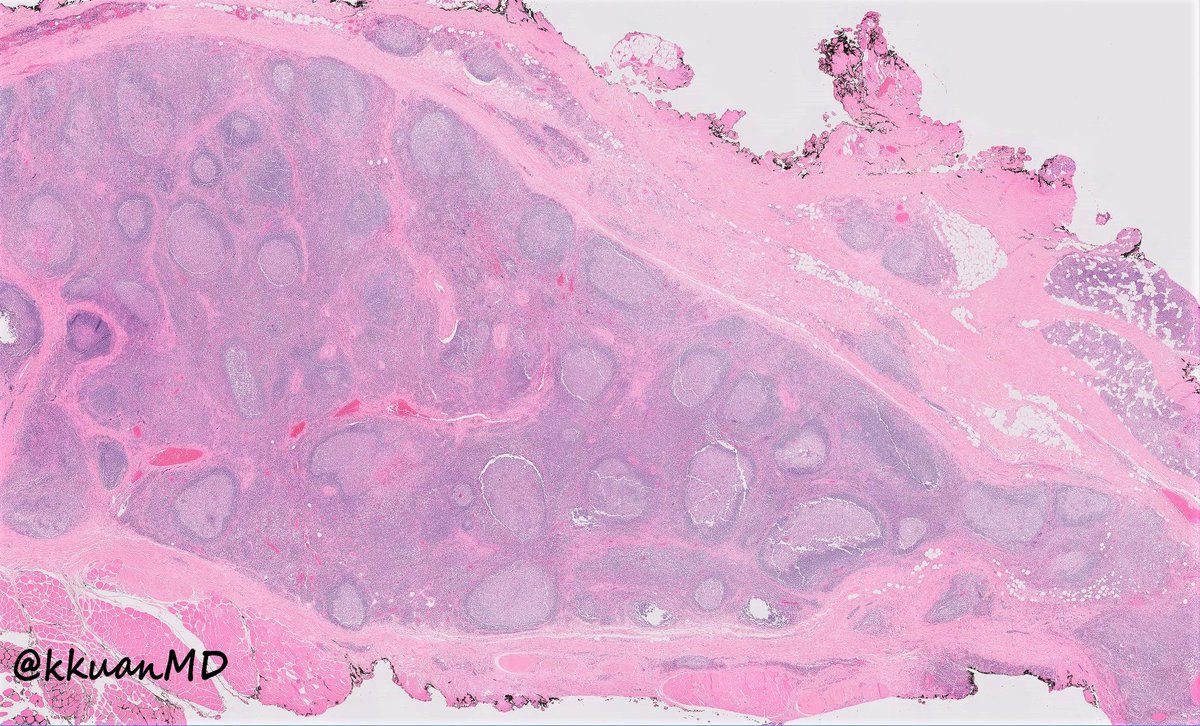

Pre-auricular nodule x 1month from 31yo patient, no other complaint. #pathtwitter #surgpath #ENTpath #hemepath #pathboards Einstein Montefiore Pathology Ridin Balakrishnan, MD Hansini Laharwani Siba El Hussein, MD Mitul B. Modi, MD Tristan Rutland MBBS FRCPA IFCAP Jerad Gardner, MD Kamran Mirza MD PhD - کامران مرزا